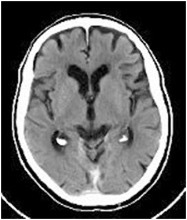

Q

Age ?

A

7-8 Y

Regular 35